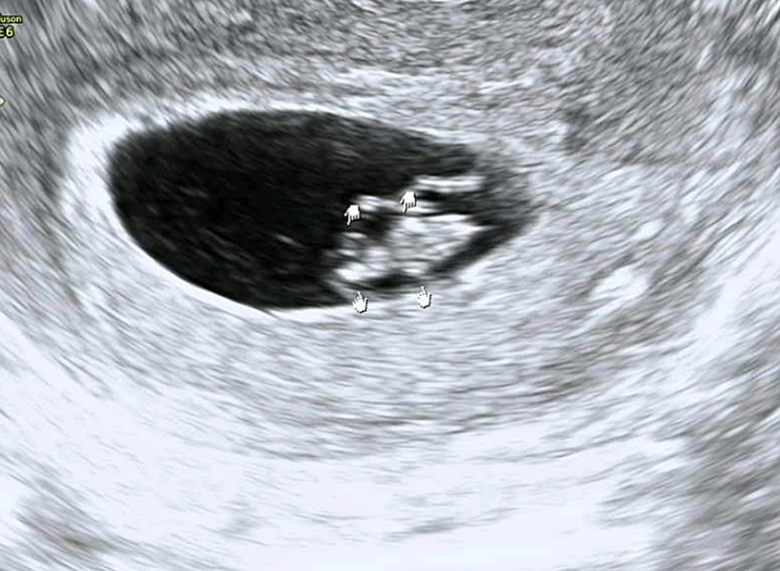

임신 8주 태아 모습 아기크기 8주차 증상

임신 8주 태아는 7주차에 비해 2배 이상 자랐고, 머리에서 엉덩이까지의 길이가 14mm ~ 20mm 이다. 태아의 크기는 2cm~2.5cm 이고, 무게는 측정할 수 없지만 약 4g 정도 된다.

머리와 몸, 두 부분으로 나뉜 2등신의 모습으로, 팔, 다리가 생긴다. 물갈퀴 같던 손발에 손가락, 발가락이 형성된다. 척추가 곧아지면서, 고개 숙인 모습에서 점차 머리를 들게 된다. 얼굴에는 눈꺼풀, 코, 윗입술이 보이고, 귀도 나타나기 시작한다.

온전한 사람의 심장 모습은 아니지만, 심장관을 통해 혈액이 태아의 전신으로 전달된다. 이 시기 태아의 심박수는 120bpm~160bpm 으로 보통 사람의 심박수보다 빠르다. 임신 후기로 갈수록 태아의 심박수는 점차 느려지지만 성인보다는 빠르다.